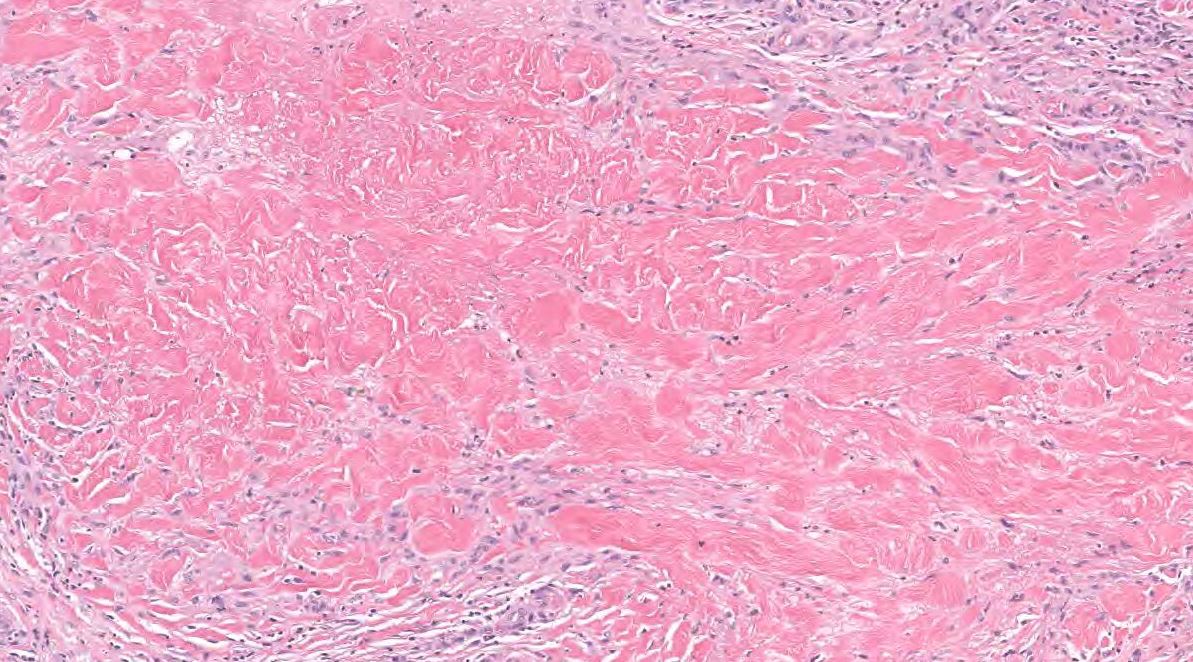

Necrobiosis lipoidica diabeticorum (NLD)

See necrobiosis in collagen